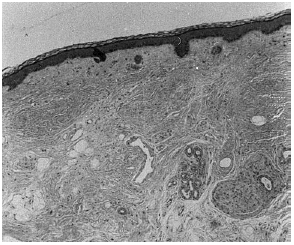

En la exploración cutánea se apreciaba, desde la glabela hasta 5 cm por encima de la línea de implantación del cuero cabelludo, una banda de aspecto fibrótico, dura y deprimida, de 11,5 cm de longitud por 3 cm de anchura, revestida de una piel lisa y brillante de color nacarado-violáceo, que dejaba ver telangiectasias superficiales y que originaba en la zona que afectaba al cuero cabelludo una banda de alopecia (fig. 1). La lesión se extendía a ambos lados de la línea media, si bien se desplazaba algo más hacia la derecha. En la exploración física no se encontraron otras alteraciones significativas.

Fig. 1.--Banda de esclerodermia lineal que afecta a la línea media desde la glabela hasta el cuero cabelludo.